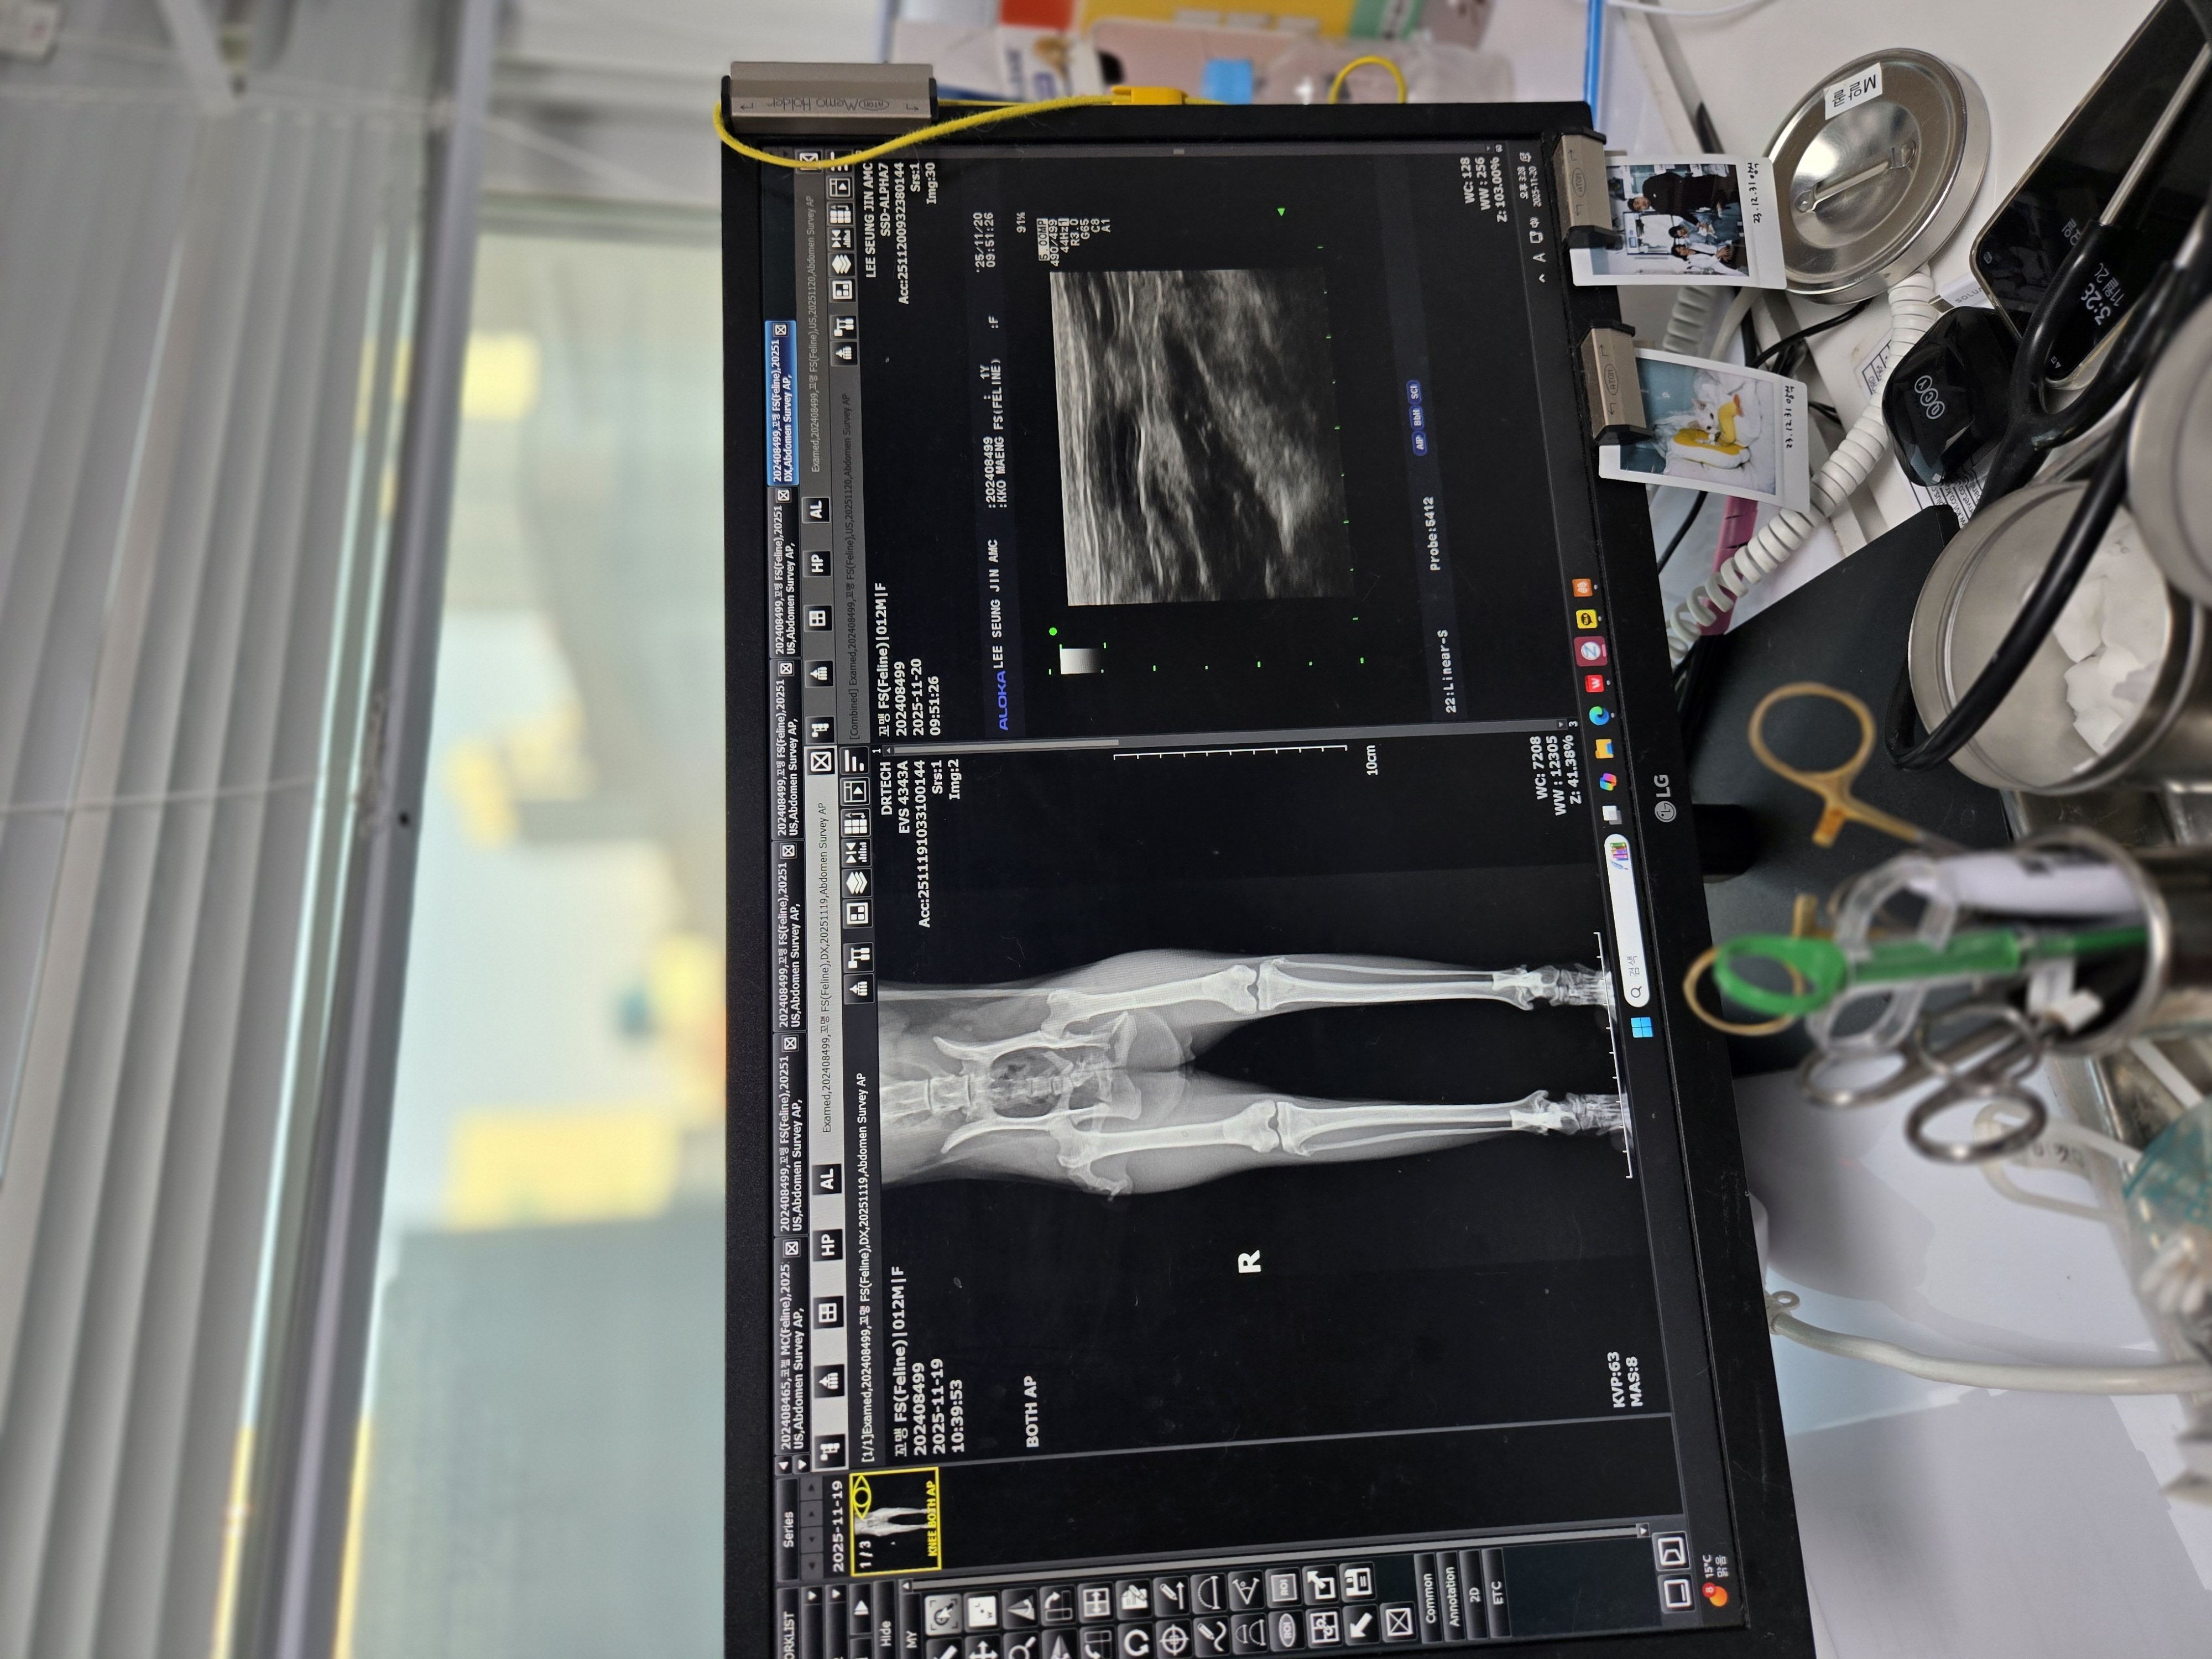

| 대상묘 병명 | (교통사고) 골반 골절 좌측 신장 신 우 확장 위 요 관 일부 확장 |

| 치료과정 | 언니가 아는 지인의 소개로 길 아이들 할인 해주는 병원 갔는데 저의 예상과는 다르게 교통사고 골반 골절 2군데이고 내부 장기 출혈의 우려가 있어서 CT나 MRA되는 2차로 가라는 거였어요 내부 장기 출혈만 없음 수술은 안 해도 된다 보행에 지장이 없는 부위기 때문에...수술은 신경이 많이 지나 가는 자리라 어려운 수술이니까 2차 병원 잘 하는데 가서 하라고... 오늘 소변이나 대변에서 피가 나오면 응급이니까 무조건 바로 2차로 가야 한다고 이렇게 듣고 나오는데 신랑이랑 저랑 멘붕이 왔어요 2차는 생각도 안하고 있었는데 어떡하지... 같이 온 언니랑 병원 소개해주신 분도 다들 병원비 걱정에 한숨...일단 집으로 왔는데 꼬맹이 소변에서 살짝 혈흔이 나와서 어디로 가나 고민 하다가 언니가 이승진도 CT MRA다 있으니 가보자 그래도 울산 서는 잘한다는 병원 이니까 그리고 어디 지원 받을 때 없나 신청도 해보자 해서 그제서야 고보협이 생각 나서 지원 신청 하게 되었어요 한번도 지원 받은 적 없고 좀 신청하기 어려워서 안 했는데 이번에 급히 신청하게 되었어요 병원 가서 원장님께 전 진료 이야기하니 엑스레이 초음파 먼저 보고 꼭 필요하면 CT나MRA 찍자고 하네요 엑스레이 초음파 혈액검사 한 후 제 예상과 달리 교통 사고는 수술 안 해도 된다 다만 뼈가 붙어야 하는데 삐딱하게 붙으면 대변 보는데 문제가 생기기 때문에 반듯하게 잘 붙도록 움직이지 못하게 가둬 두라고 하셧어요 근데 더 심각한 다른 병이 발견 되었어요 좌측 신장 신우 확장 요관 일부 확장 원장님이 그림 그리면서 설명 해 주시는데 신장 밑에 관하고 연결된 부위 관 윗부분 부분 확장 신장 밑 천공 일단 수액 항생제 3일 치료 후 먹는 먹는 항생제 5일 먹고 재검해 보고 결과보고 이야기 하자고 하셨어요 질염도 있다고 ...저녁에 문자 왔는데 뇨 검사상 혈액 염증 세포 검출 된다고 직접적인 세균은 확인되지 않지만 가능성 있다고 신우 신염에 준하여 치료하겠다 이렇게 왔어요 입원 시키고 3일 동안 면회 갔는데 거의 움직임이 없고 살도 좀 빠진 상태 매일 사진과 컨디션이 카톡 으로 오는데 아이는 순한데 사람 보이면 숨고 움직임이 없다 퇴원하고 집에 와서도 똑같아요 캐리어 들어가서 나오질 않아요 얼굴 구경 하기가 힘 듬 하기야 골반 뼈 두 군데나 골절 되었는데 얼마나 아프겠어요? 약은 항생제 캡슐에 츄르 묻혀서 항상 잘 먹어 왔는데 이날 따라 입안에 붙었는지 씹다가 약이 터져서 거품 물고 난리가 나서 병원에 전화했더니 대게 쓴 약이라네요 다음 날부터 약만 골라내고 안 먹어서 병원 가서 물약으로 된 항생제 다시 받아 왔어요 다행히 이건 잘 먹네요 29일이 재 검 일이라 다시 다녀 왔는데 신우 확장하고 요관 확장은 낫지 않을 꺼 같다 하네요 원인도 모른다 하시고 다만 추측으로는 선천적 기형일 가능성과 TNR 했을때 잘못 되었을 가능성 그냥 추측일 뿐 이라 하셨어요 나빠지지 않으면 좋지만 만약에 좌측 신장 기능을 잃어도 하나는 정상이니까 사는데 지장 크게 없다 하네요 다만 염증은 신장을 다 상하게 하기 땜에 치료가 꼭 필요하다 하고 아직 질염도 있고 백혈구 수치가 높으니 2주 항생제 더 먹어보고 다시 검사 하자고 하시네요 15일 오전에 예약 잡아 놓고 왔어요 |

엑스레이랑 초음파 보고 왔구요

뼈는 잘 붙고 있는 중인데 왼쪽 다리를 안쓰니 양쪽 다리 근육 굵기 차이가 나서 원래는 재활을 해야 하는데 고양이는 재활이 안된다네요

그래서 진통제 2주간 먹으면서 움직여야 한대서 약 2주치 처방 받아 왔구요

아무래도 신장 한쪽은 기능이 천천히 소멸할 것 같다고 하네요 ( 아직도 백혈구 수치가 약간 높음) 한쪽이 정상이니 사는덴 지장이 없다네요